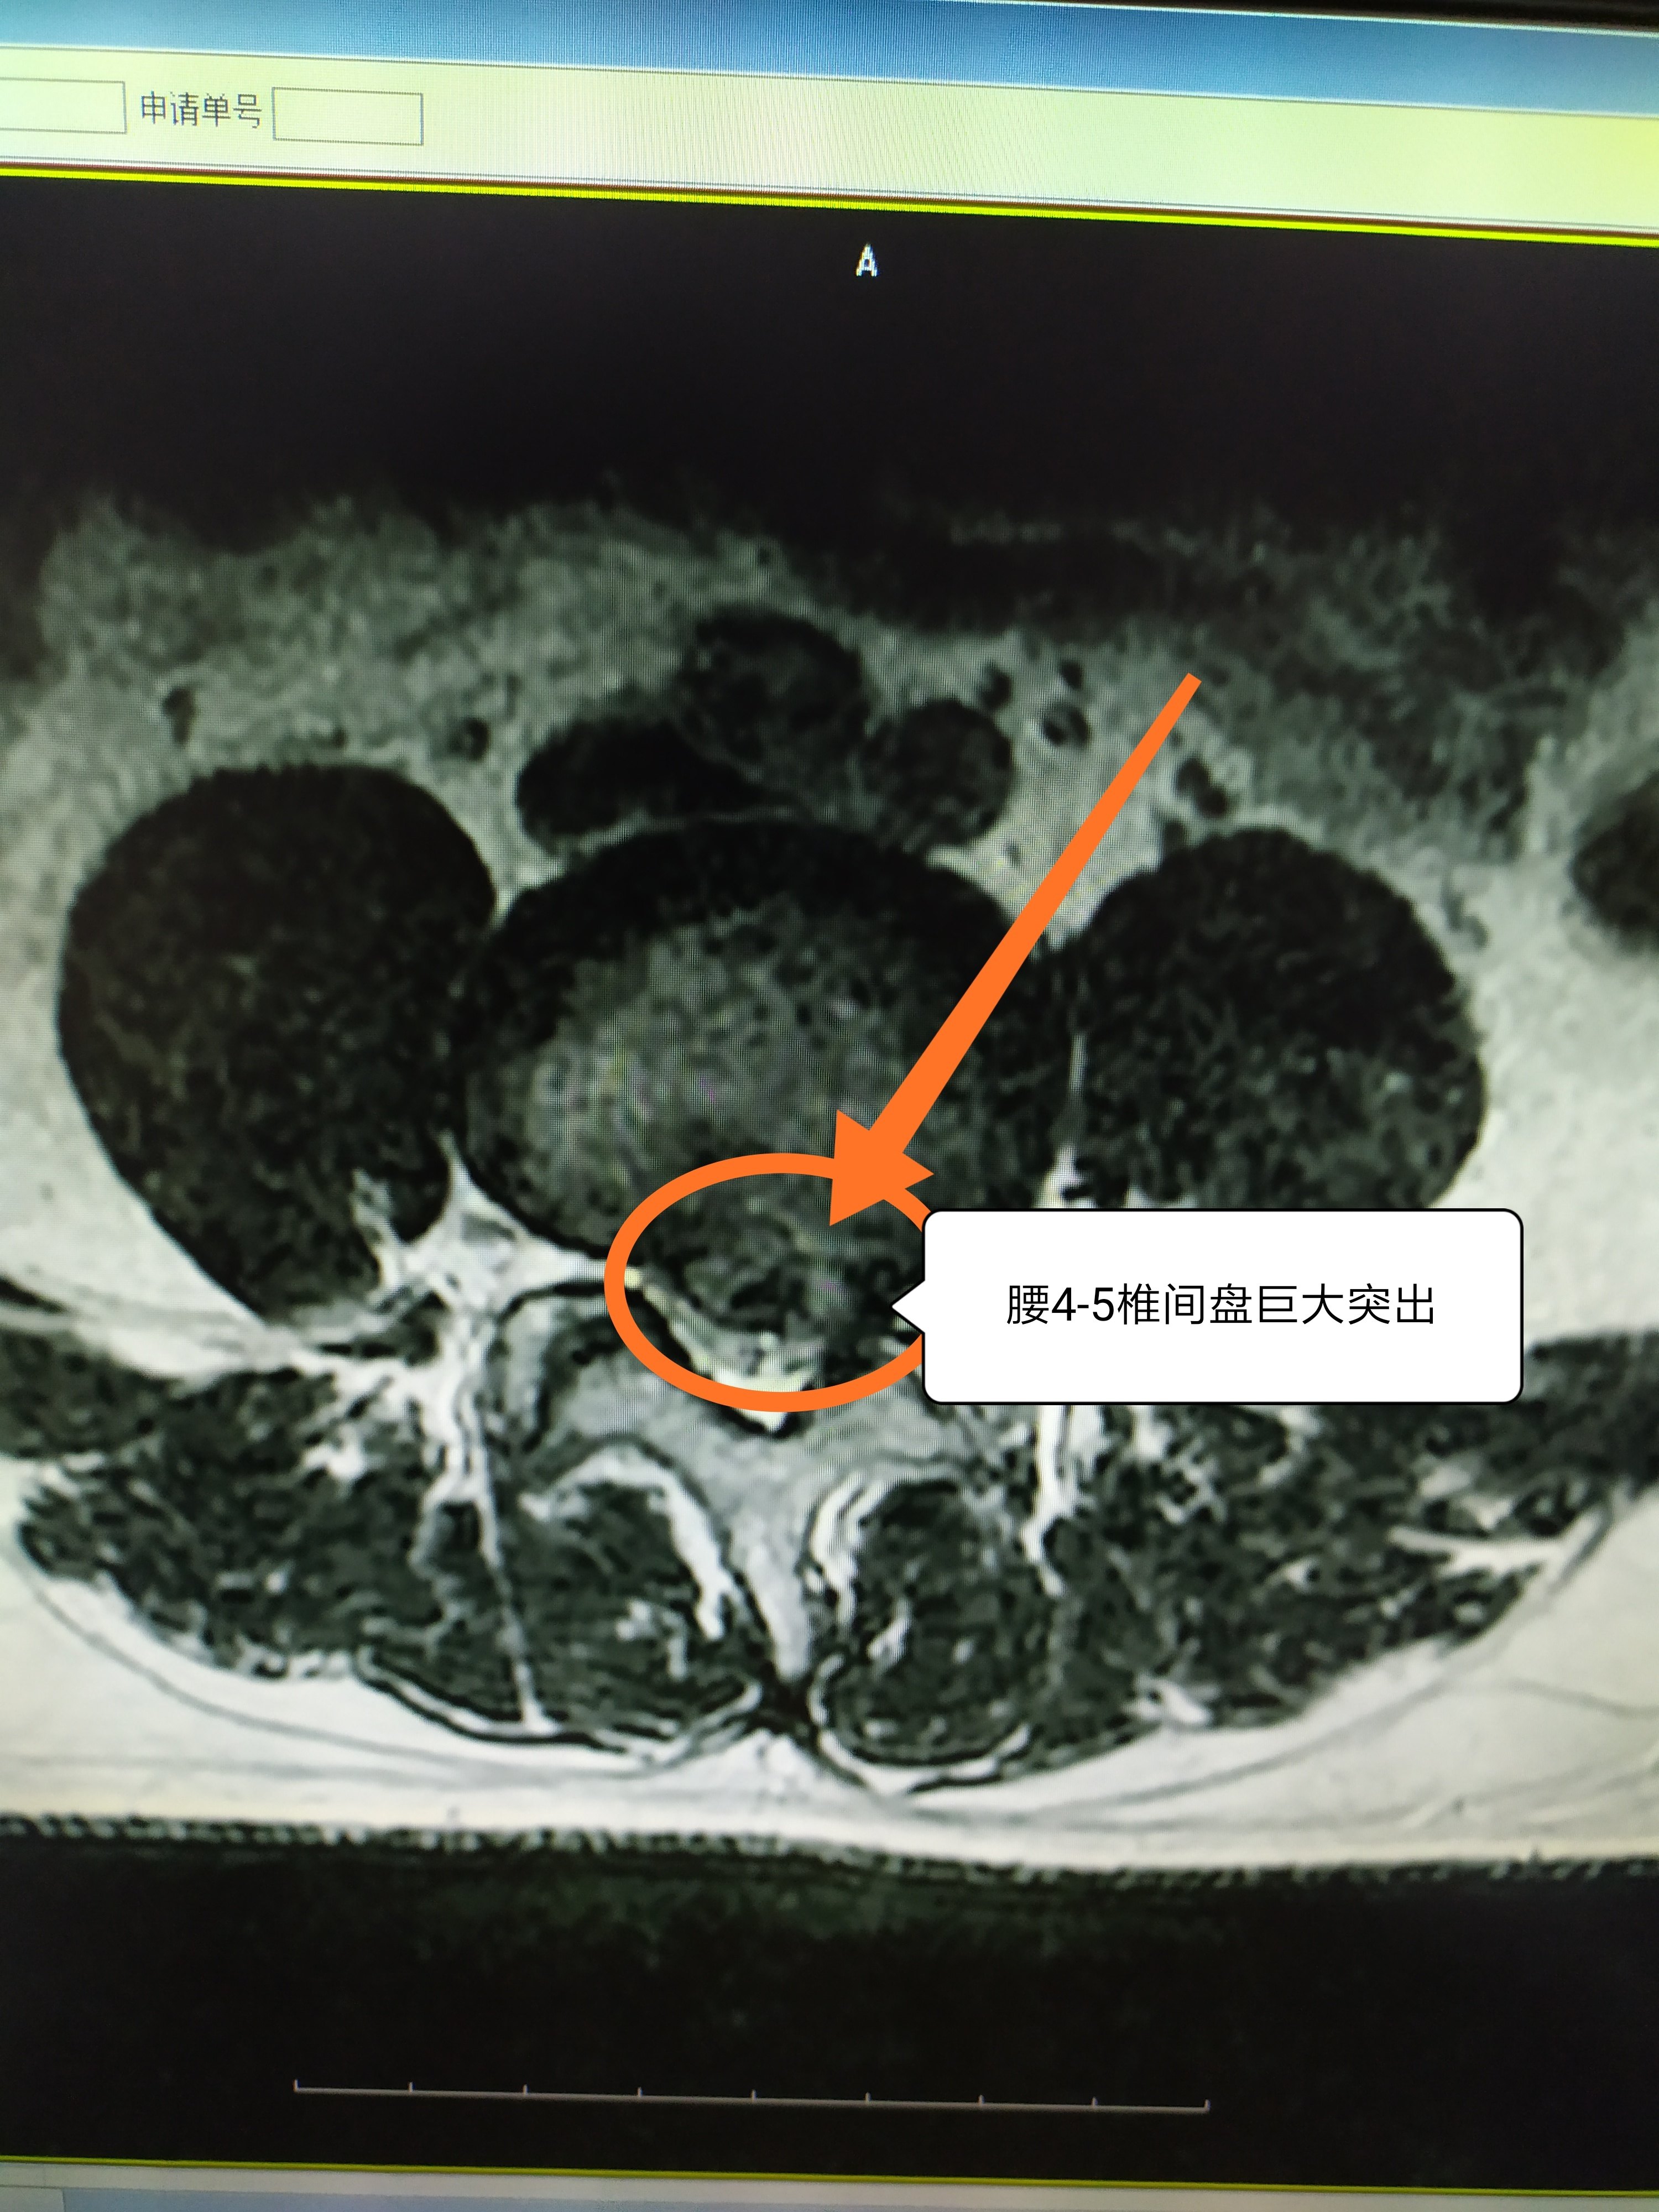

临床上最常用,也是对临床治疗最具有指导意义的一种分类方法,就是按照椎间盘突出的严重程度,从轻到重依次分为四种类型:膨出型、突出型、脱出型以及游离型的椎间盘突出。

腰突最开始的阶段属于膨出型。一支新牙膏,口子上有封口膜。如果这个封口膜没有破,牙膏是挤不出来的。膨出型的椎间盘,外层的纤维环是好的,它没有破裂,内层的髓核组织无论怎么压,它也只会把纤维环向外顶出。基本上,如果超过40岁的人去做腰椎的核磁共振检查时,一半以上的人,都会有不同程度的椎间盘膨出。